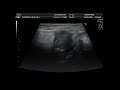

Грыжесечение – это хирургическая процедура, которая используется для лечения грыжи. Грыжа возникает, когда орган или ткань выступают за пределы своего нормального положения через слабое место в мышцах или тканях, которые обычно удерживают их на месте.

Грыжа может возникнуть в разных частях тела, таких как живот, пах, пупок или бедра. Она может вызывать дискомфорт, боли и ограничивать функциональность пациента.

Процедура грыжесечения выполняется с помощью хирургического вмешательства, во время которого хирург возвращает выступающий орган или ткань внутрь тела и укрепляет слабое место тканей, где возникла грыжа. Это может быть достигнуто с помощью швов, использования специальных сеток или комбинации этих методов.